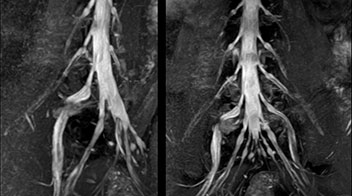

At Northern Fukushima Medical Center in Japan, excellent MRI visualization of nerves helps support confident diagnoses and informs surgical treatment decisions for patients with lower limb symptoms. MRI technologist Tanji and orthopedic surgeon Dr. Yabuki share how direct nerve visualization with the 3D NerveVIEW method adds information when diagnosing atypical herniations. The additional insights changed their way of working and benefit their patient care, as illustrated by some clinical examples.

“In patients with lower extremity neurological symptoms, NerveVIEW helps us to determine the disease matching the patient’s symptoms by directly visualizing the nerves. We use the sequence mainly, when there is suspicion of intraforaminal stenosis, extraforaminal stenosis or lateral disc herniation, which is often based on routine T2- and T1-weighted images. Additionally, the excellent depiction of the course of nerves makes NerveVIEW a good navigator when applying treatment such as block therapy or surgery.”

“In such case, we would then browse through axial T2-weighted MR images slice by slice and mentally reconstruct the actual situation based on both radiculography and MRI. Fortunately, NerveVIEW can now very well show nerve courses and presence of nerve compression or edema in one single image series.” “We have often seen NerveVIEW directly depict details of the nerve compression that were not observed by radiculography. Therefore, we think that with NerveVIEW we can reduce the number of invasive examinations, especially for some patients with lumbar plexus symptoms.”

The key concept in MR neurography, Dr. Yabuki stresses, is the ability to directly visualize spinal nerves, versus inferring the presence of pathology indirectly. “Before NerveVIEW, we estimated compression of the nerve by looking for the presence or absence of fat signal on other MR images,” he says.

“For example, in sagittal images, when the presence of fat is observed in the intervertebral foramen, it suggests that there is a margin around the nerve. Similarly, the absence of fat indicates that the nerve is being compressed. So, we used to deduce nerve compression indirectly. With NerveVIEW, however, we can observe the condition of the nerves directly, regardless of the presence or absence of fat. We always prefer such direct observation of anatomy over having to make an inference about it.”